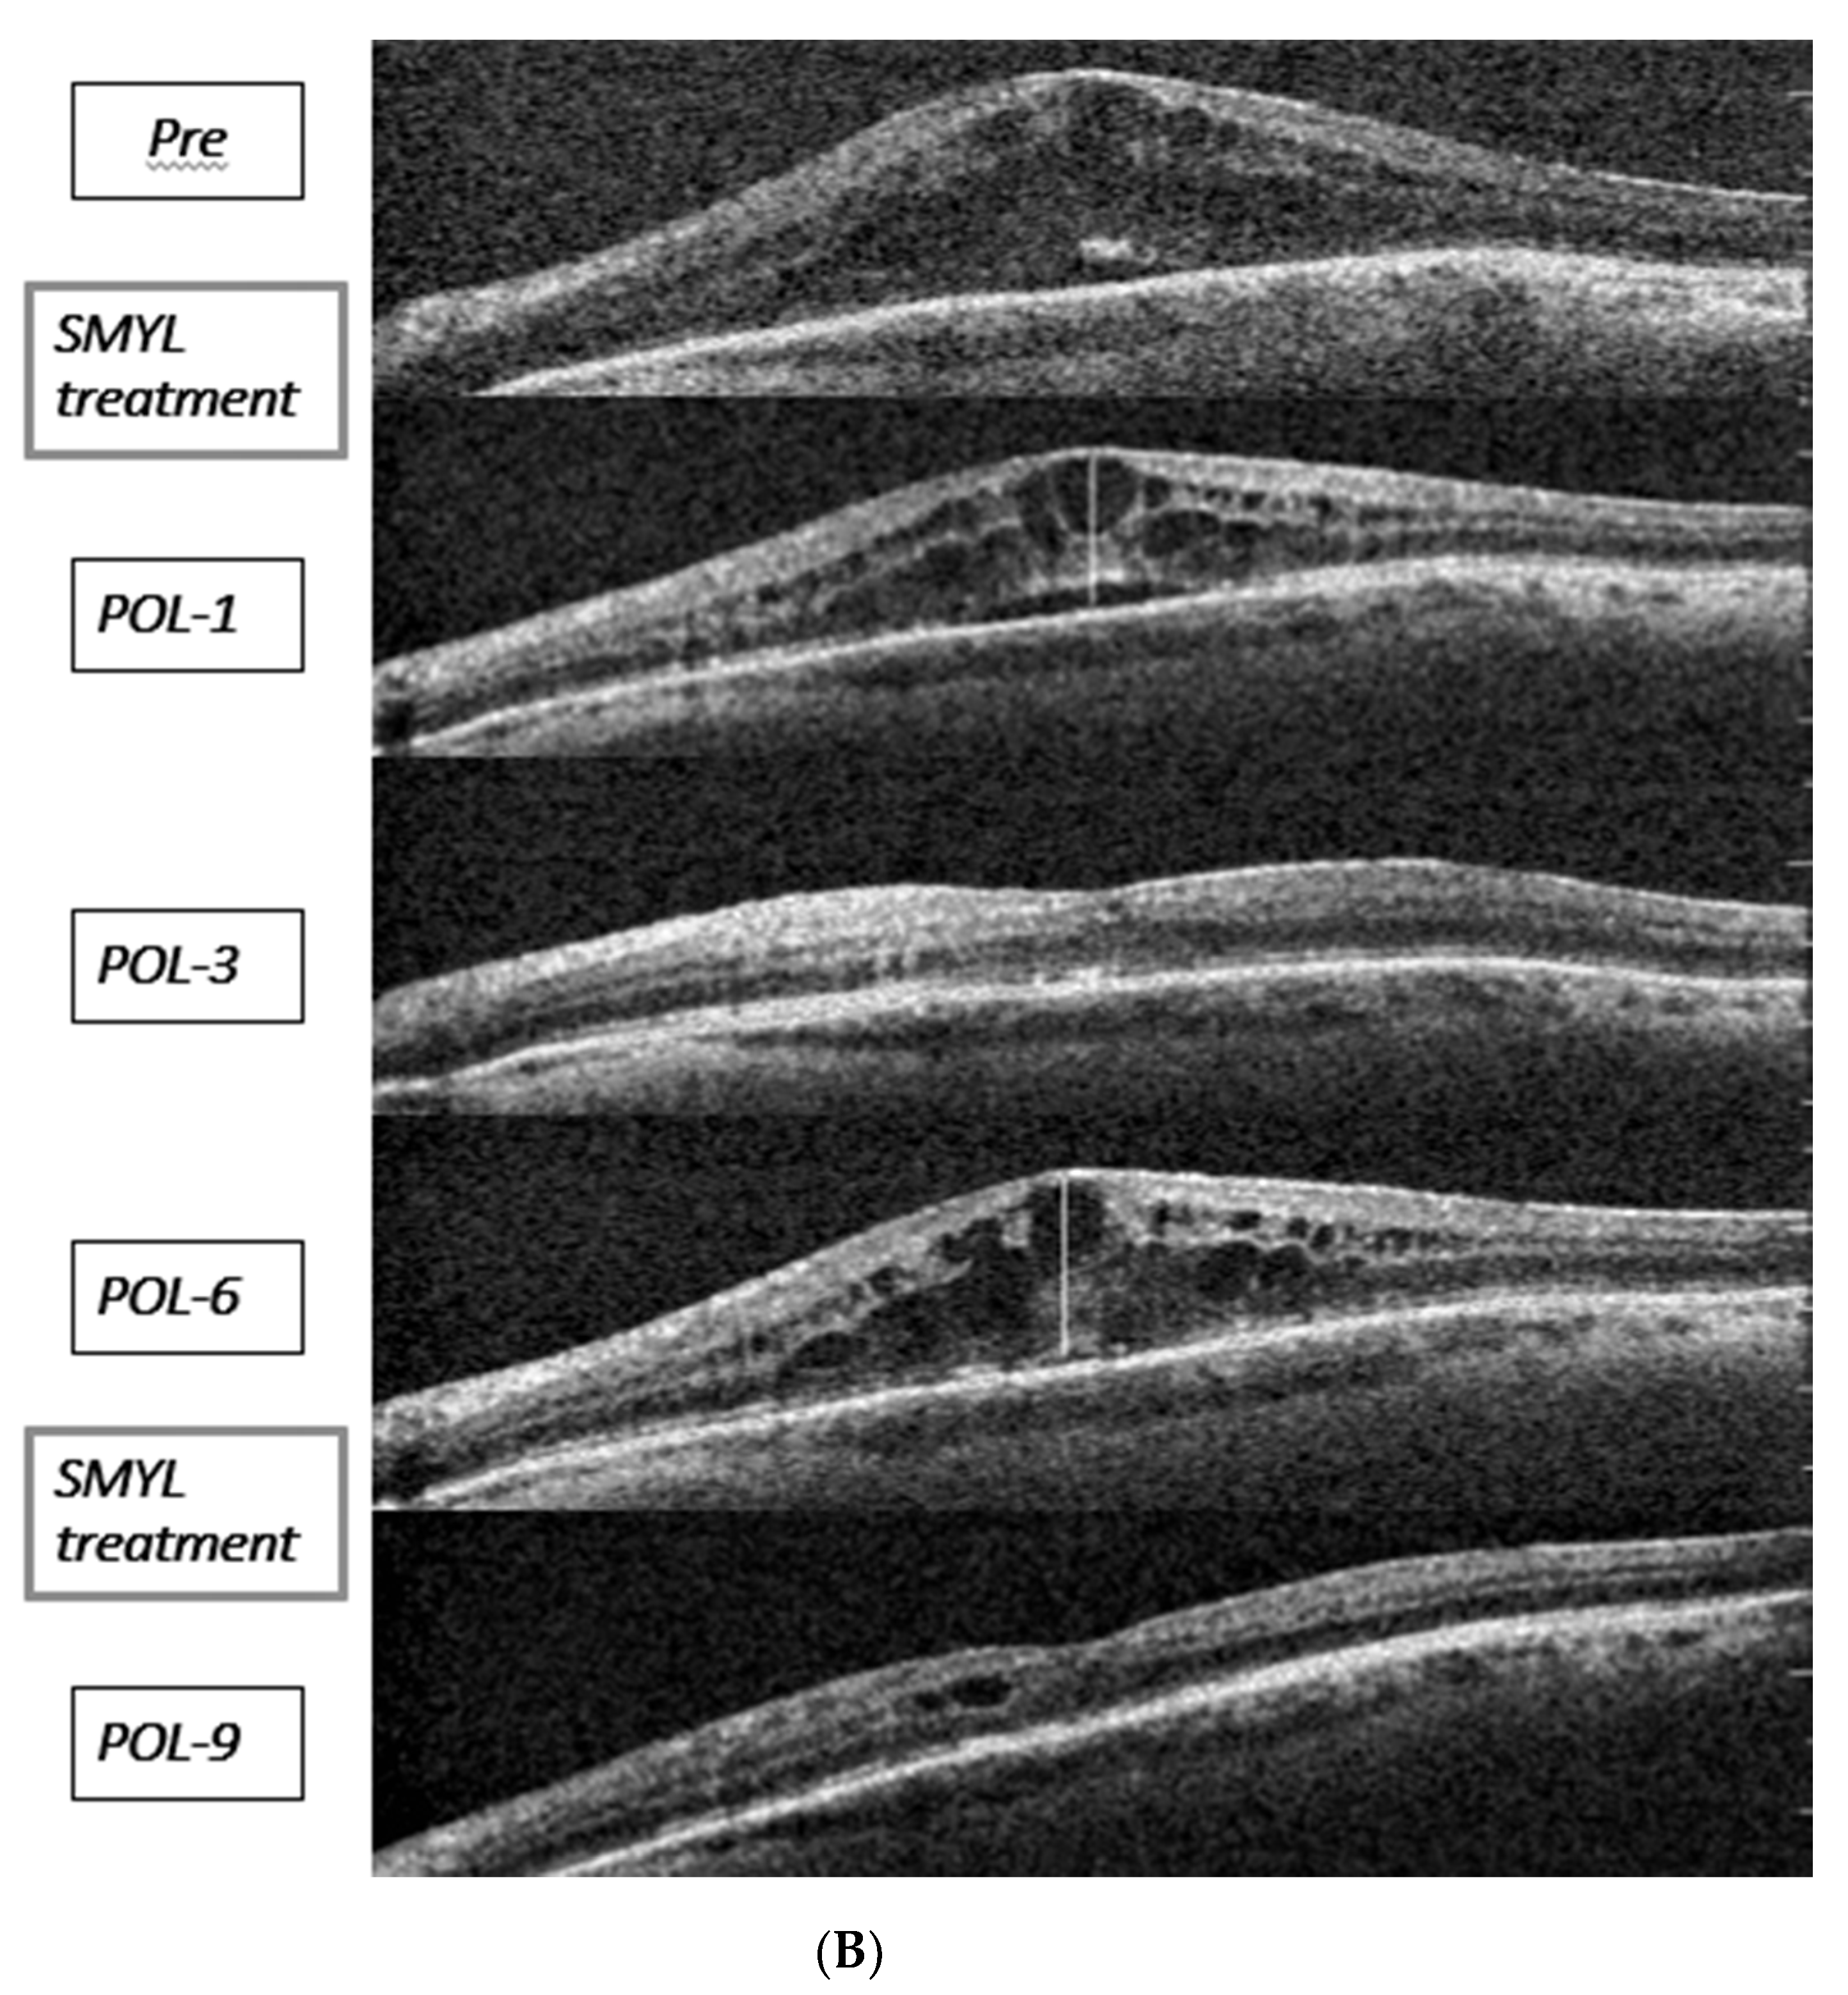

| P6 | 79 | OD | CC | Phaco/IOL and PC-R +Scleral fixation same IOL | 16 | NSAIDs, 3 TA | 0.52 | 532 | 3 |

| P8 | 73 | OS | RD (m-Off) | PPV + SO | 13 | 1 TA, 1 Ozurdex | 1.30 | 600 | 2 |